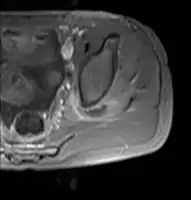

![]() | |

| Transverse T2 magnetic resonance imaging section through the hip region showing abscess collection in a patient with pyomyositis. | |